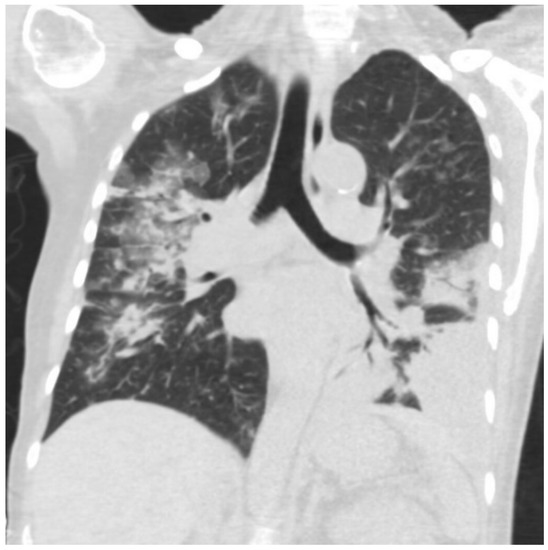

2. Case Presentation

3. Investigations